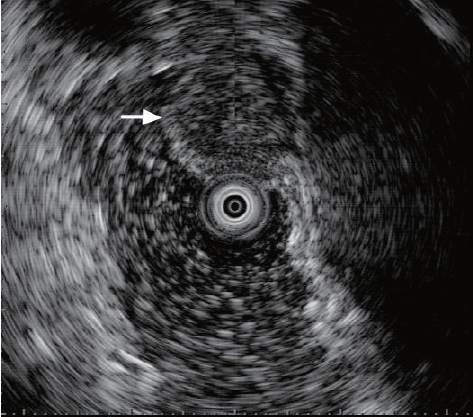

超声内镜提示,不均匀低回声病变起源于固有肌层,边界尚清晰,形状欠规则,截面测量为17mm×9.7mm,考虑为间质瘤(源于固有肌层)(图3),为进一步治疗收入院。

图3 超声内镜:不均匀低回声病变起源于固有肌层,边界尚清晰,形状欠规则,截面测量为17 mm×9.7 mm(白色箭头)